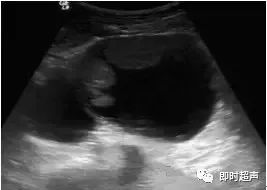

小婷繼續問道:醫生,左卵巢卵黃囊瘤伴巧克力囊腫應該怎么預防呢?雌激素水平失調:卵巢內分泌調節混亂,雌激素分泌過剩,使卵巢內的卵泡不能正常發育,從而形成卵黃囊瘤。...